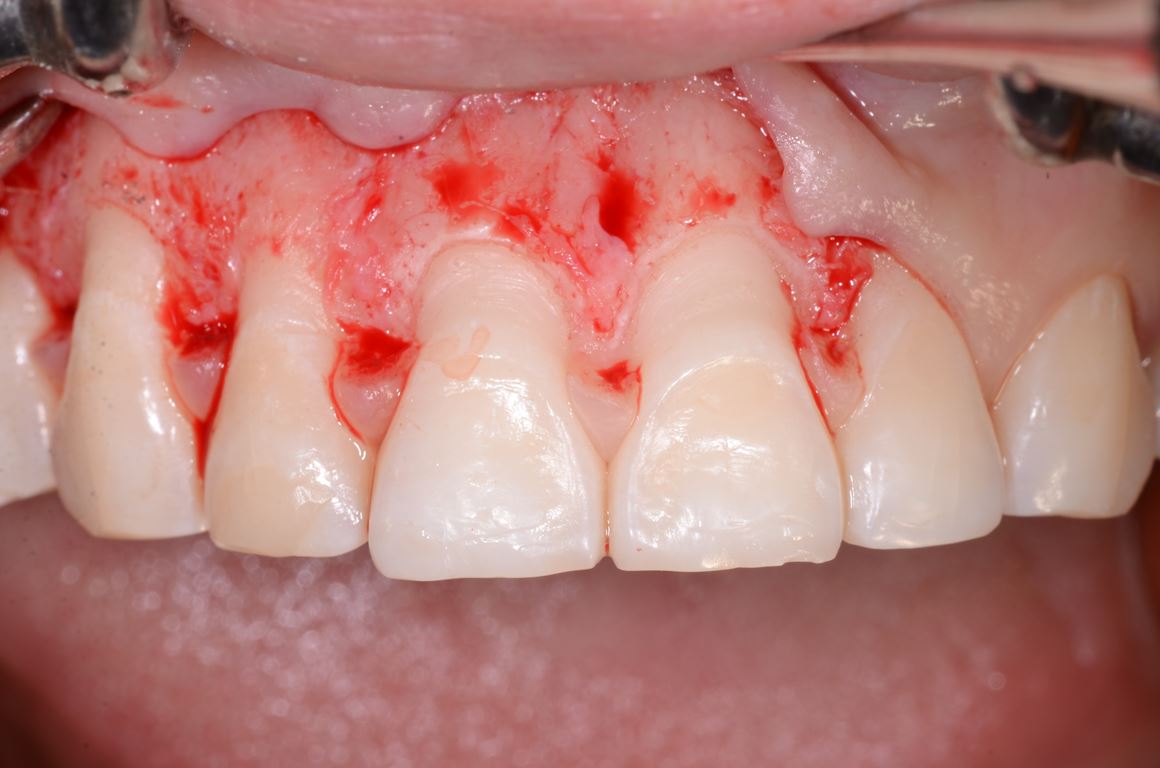

Analiza fotografii z mock-upem potwierdziła konieczność wydłużenia koron klinicznych wszystkich zębów przednich o około 2 mm w kierunku dokoronowym oraz zębów 13-21 w kierunku dowierzchołkowym, w celu zharmonizowania poziomu zenitów dziąsłowych. W związku z tym w okolicy zębów 13-21 wykonano zabieg chirurgicznego wydłużania koron (ryc. 28, 29).

Po 6 miesiącach od zabiegu chirurgicznego rozpoczęto leczenie protetyczne mające na celu odbudowę prawidłowej anatomii zębów i odtworzenie utraconej funkcji żucia. W pierwszym etapie zaplanowano rekonstrukcję górnego łuku zębowego, wzorując się na wcześniej wykonanym woskowaniu i mock-upie. Preparacja przez mock-up pozwala na minimalnie traumatyczne szlifowanie, co jest szczególnie istotne w przypadkach takich jak przedstawiony, gdy już doszło do znacznej utraty tkanek na powierzchniach żujących zębów bocznych (16) (ryc. 30). Przed wykonaniem docelowych rekonstrukcji ceramicznych sprawdzono wyfrezowany z żywicy akrylopolimerowej (PMMA) prototyp z jednocześnie założonym na dolny łuk zębowy mock-upem (ryc. 31).